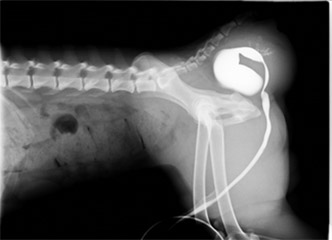

来院時、肛門右脇が大きくふくれており、レントゲン検査にて膀胱が反転してヘルニア嚢に嵌頓しておりかなり重度の状態でした。

来院時レントゲン検査:重度の便秘および膀胱の反転が認められました。